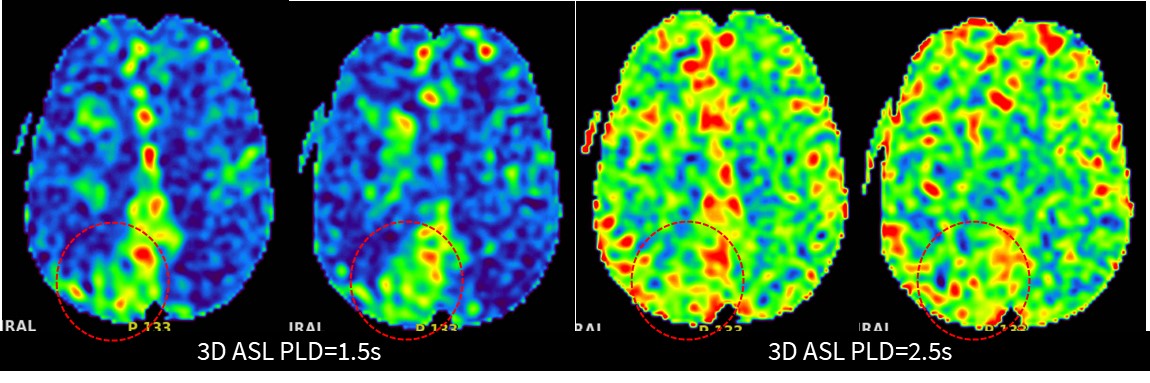

大部分影像科可能这时都会让患者回科室,把疑问留给临床医生琢磨了。但我院影像中心本着精准医学,精准影像先行的宗旨,不折腾患者来回跑,尽量一次折腾明白,继续扫描不打药灌注3D ASL:

3D ASL PLD=1.5s显示双侧大脑灌注相对减低,PLD=2.5s双侧大脑灌注恢复,说明存在灌注代偿,且右侧顶枕叶呈现高灌。

3D ASL为我们解答了为何患者血管大面积不显影,DWI上没有新发病灶,综合PLD=1.5s和2.5s来看患者虽然双侧大脑中动脉和大脑前动脉闭塞,但有灌注代偿,并未影响大脑供血;右侧顶枕叶呈现高灌,也印证了在TOF MRA上看到的右侧枕叶粗大的侧枝血管有代偿供血。到这一步基本解答我们的疑问,或许我们还需要一些直接的征象来证明我们的判断。SilenZ MRA(静音血管)也许能让我们看到更多的信息: